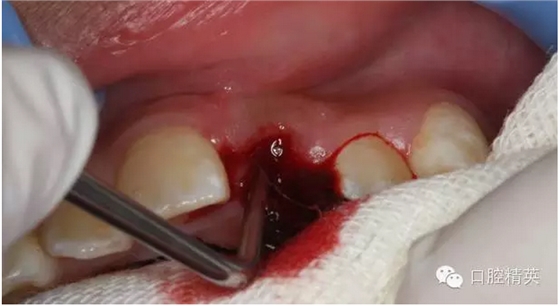

圖13.清理21牙槽窩